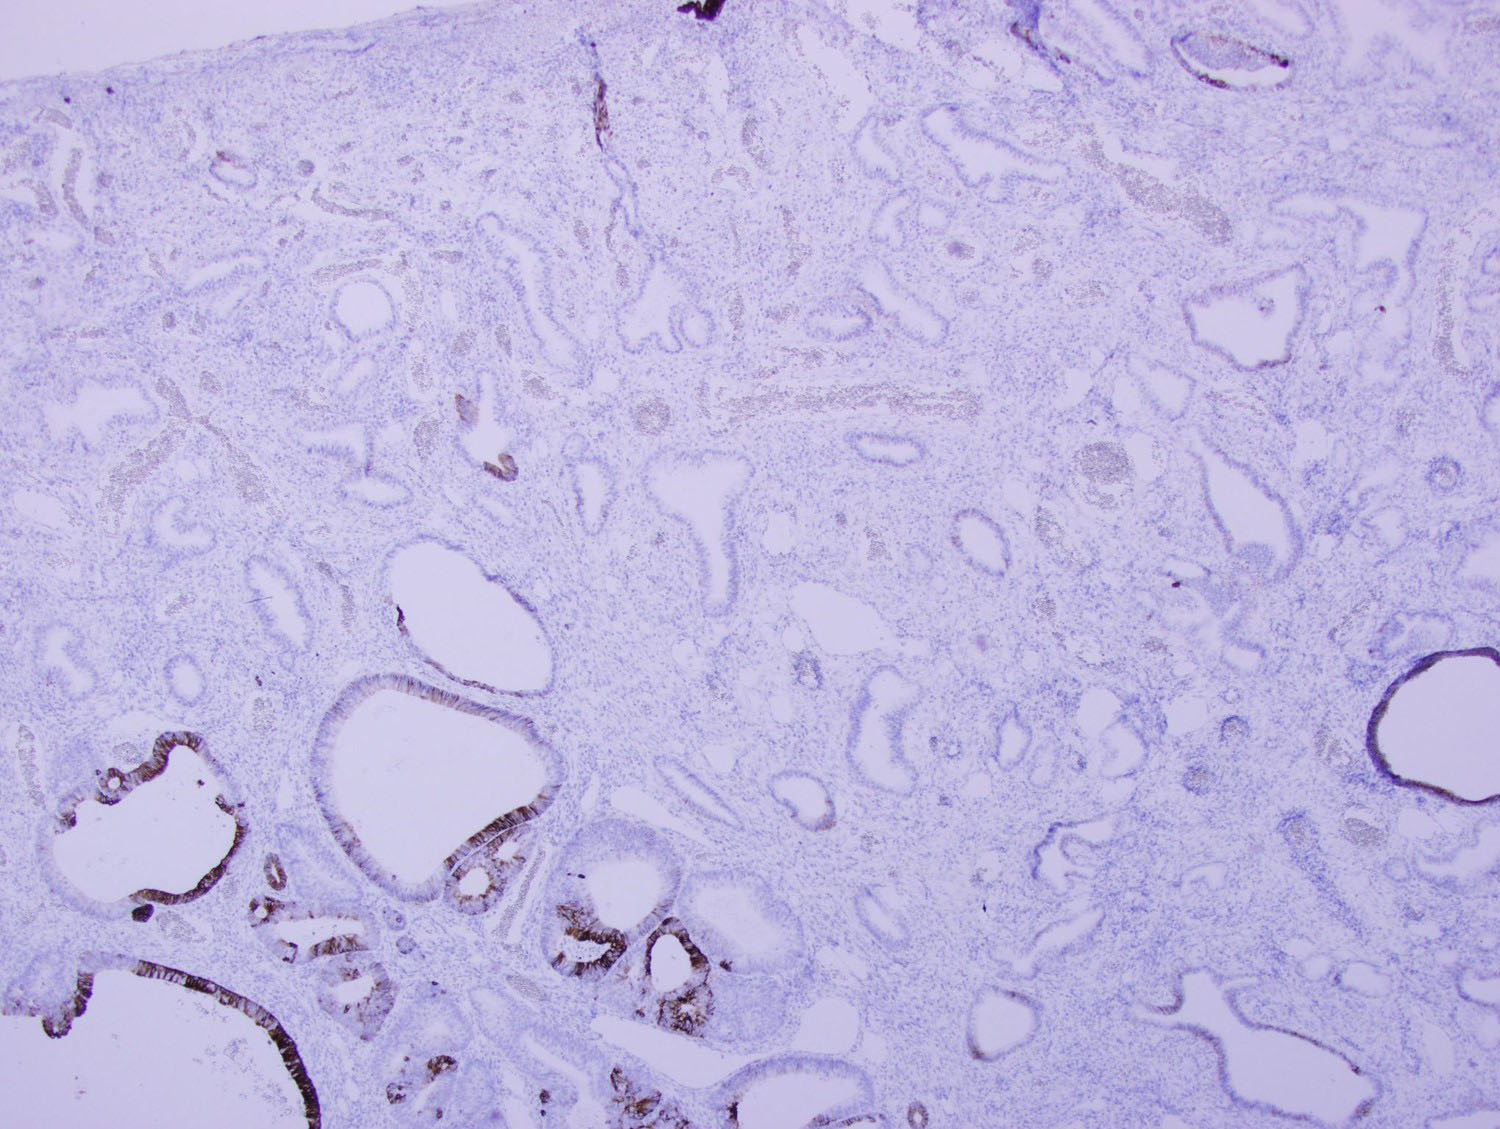

Microscopic examination of the sigmoid polyp demonstrated complete replacement of the normal colonic mucosa with infiltrating angulated and irregular glands lined by benign pseudostratified columnar epithelium, some of which were cystically dilated (Figures 2-4). Surrounding these glands was a characteristic spindle cell stroma admixed with inflammatory cells and prominently dilated vasculature. Immunohistochemical (IHC) stains were performed. The glands were negative for CDX2 and CK20 (Figures 5 and 6), while positive for PAX8 (Figure 7) and focally strongly positive for CK7 (Figure 8). The surrounding stroma was focally positive for CD10 (Figure 9).